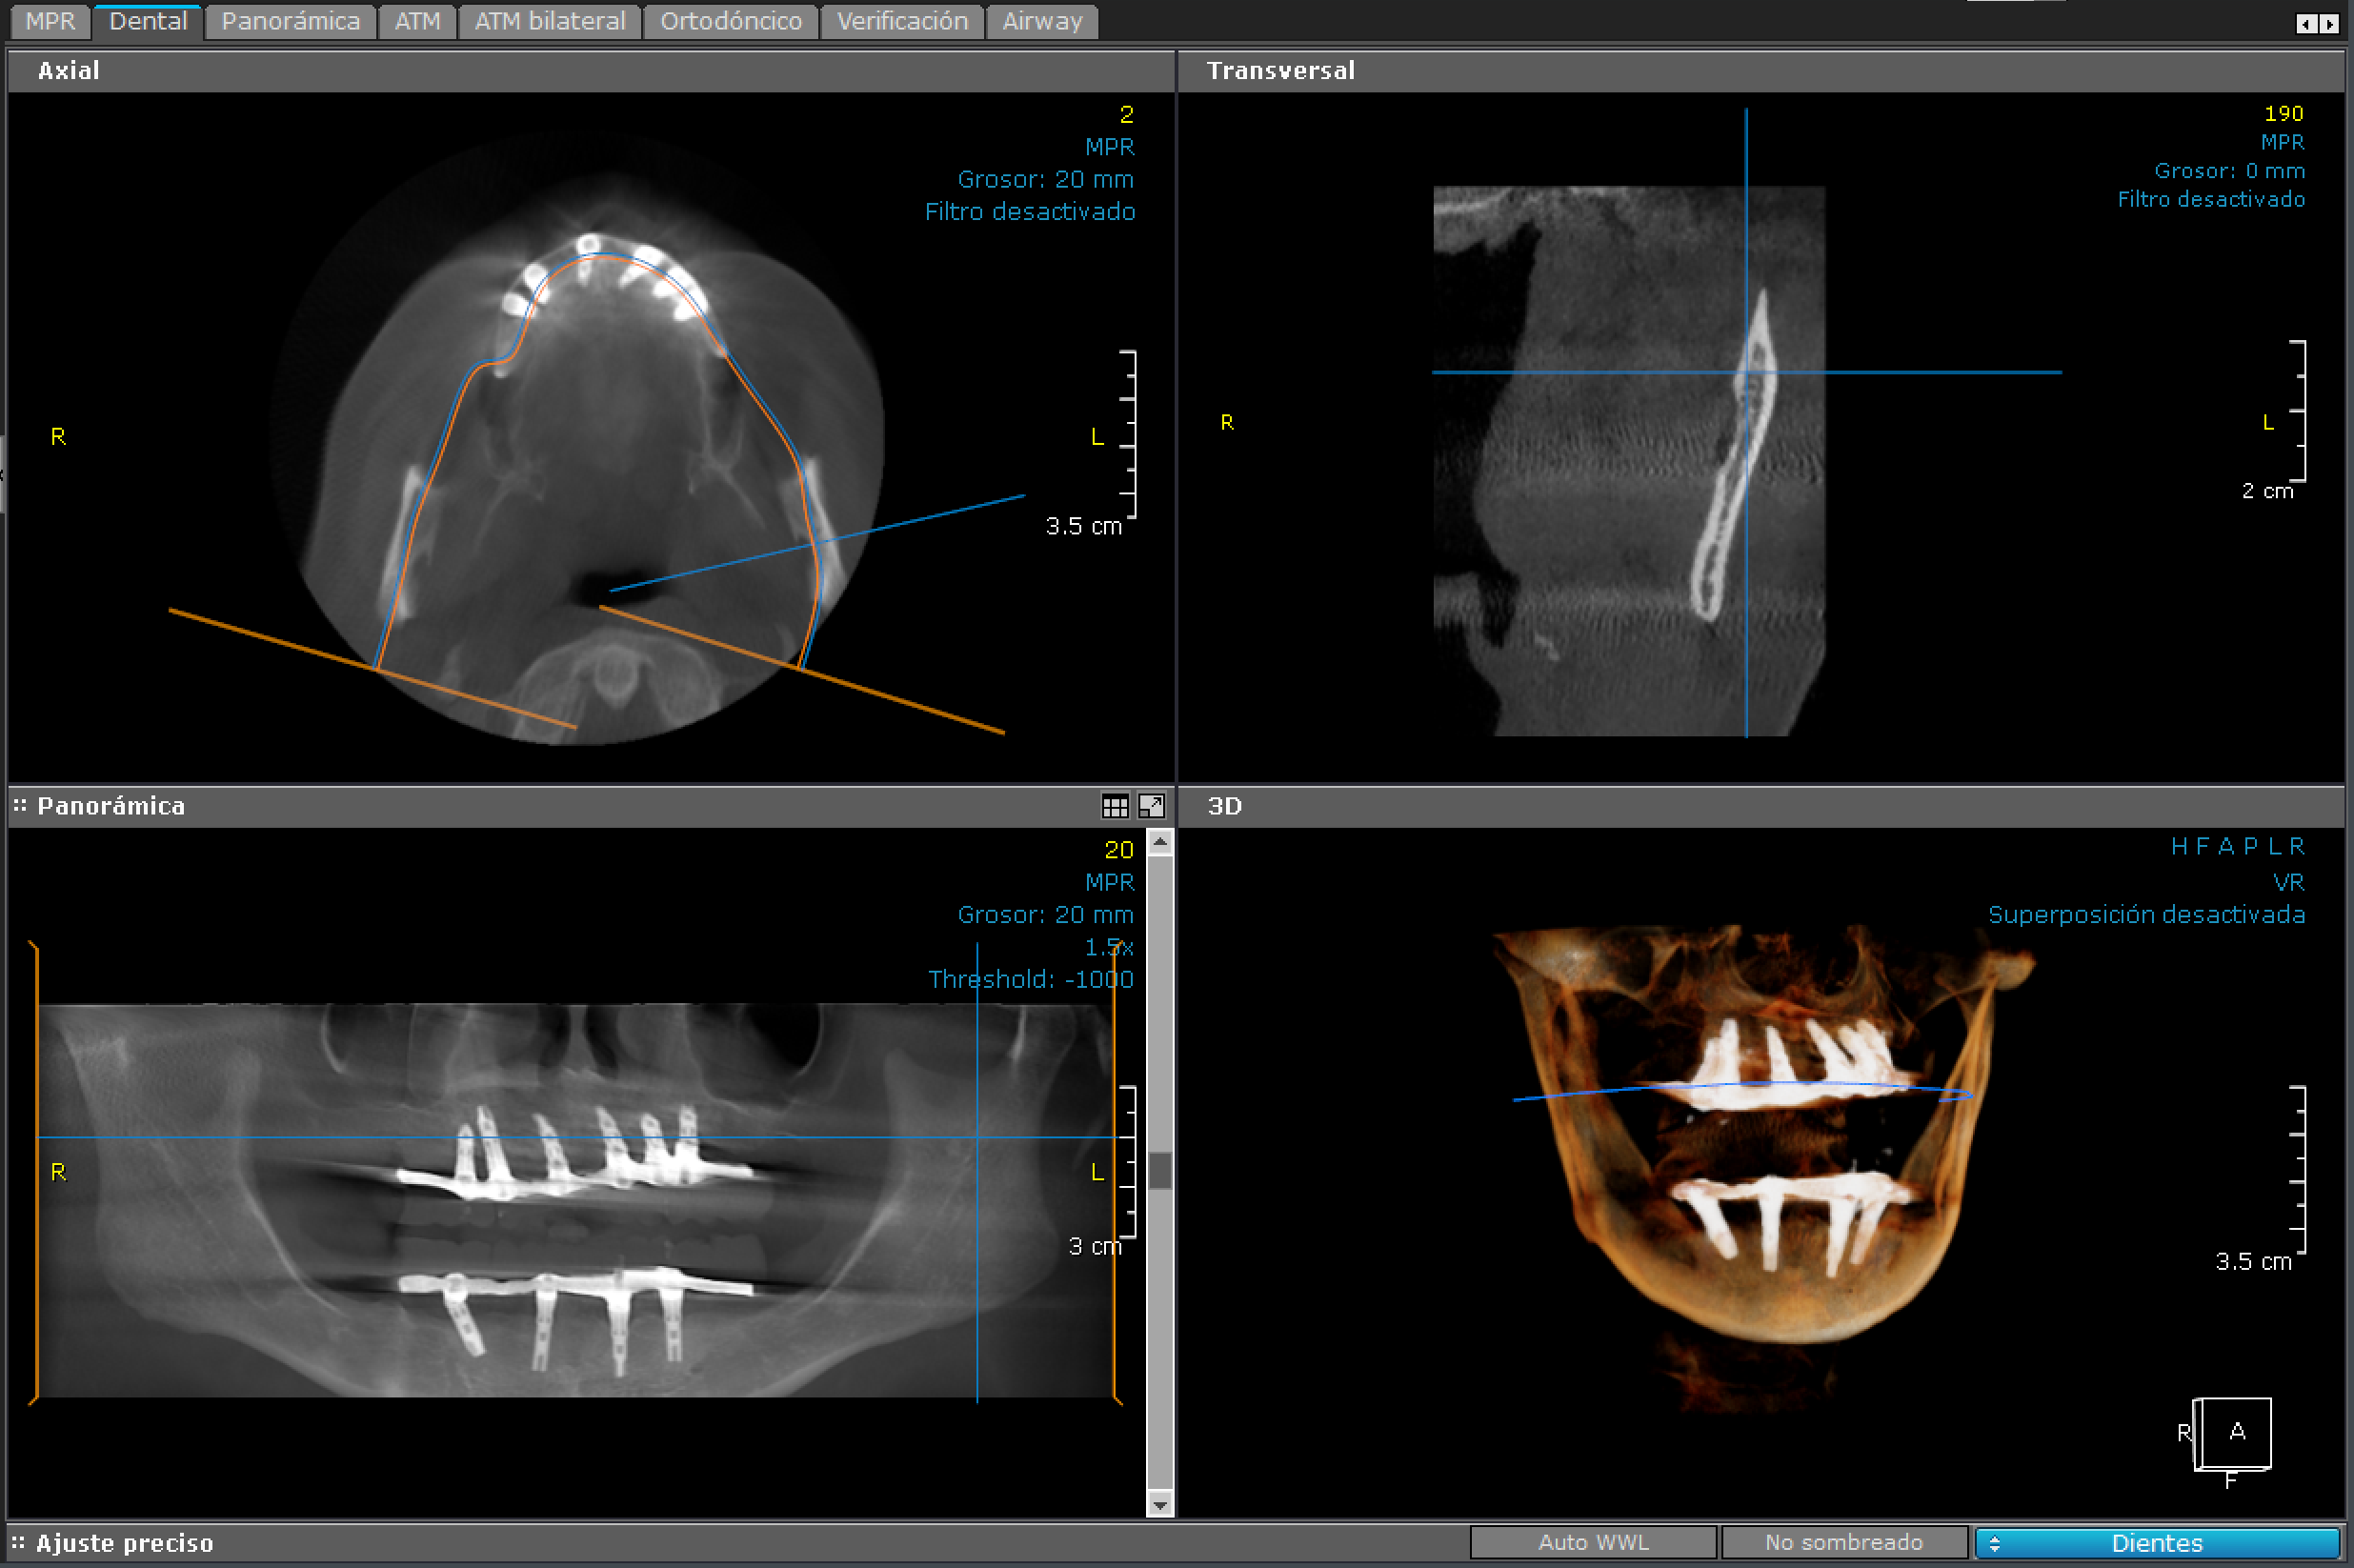

3D - Bimaxilar

bimaxilar

Es un examen radiológico computarizado de ambos maxilares. Es de especial ayuda para la planificación de cirugía dentales.